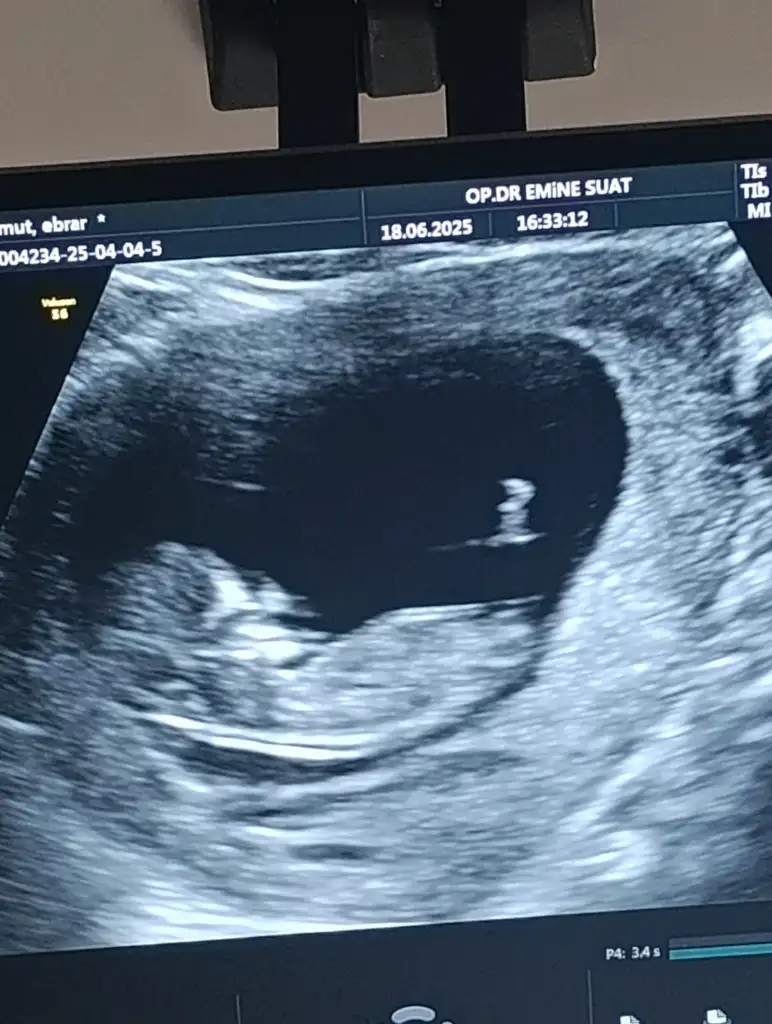

Evet evet benim rahim hemen düzelmişti zaten erken dönem kürtajdı ya, 30-31inde çatlamayı gördüğümü düşünürsek tam 14 gün sonra regl gelmiş oluyo. Ama feci ağrılı gececek gibi bakalımYaaaa bu ay tekrardan dene kürtajdan sonra rahmine baktırdın mı ki herşey normale dönmüş mü diye